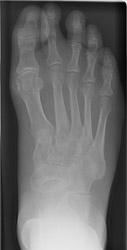

CPPD: AP - Faint calcifications at 1st MT headCPPD: AP - Faint calcifications at 1st MT head CPPD DISEASE (PSEUDOGOUT) calcium pyrophosphate dihydrate deposition within cartilage and peri-articular structures.

First metatarsophalangeal joint involvement is most common in forefoot. The talonavicular joint space is commonly affected with hind foot involvement. The distribution pattern for CPPD is usually bilateral, and may be symmetric or asymmetric.

Variable, inconsistent osteophyte formation can occur with this disease. Numerous, large subchondral cysts may progress to micro fractures, collapse, and formation of intra-articular bodies. Calcific tendonitis (especially of the Achilles tendon and plantar aponeourosis), or metatarsophalangeal joint capsular or synovial calcifications may be present. Associated calcifications of the bursa, ligaments, and fibrocartilaginous structures of the foot are less common.

Joint destruction and cyst formation may resemble osteoarthritic findings. Talonavicular joint fragmentation may mimic neuropathic arthritis. Synovial calcifications and soft tissue swelling may be confused with gout. Tendinis calcifications may mimic calcific tendonitis secondary to calcium hydroxyapatite crystal deposition disease, and these conditions are commonly co-existent.